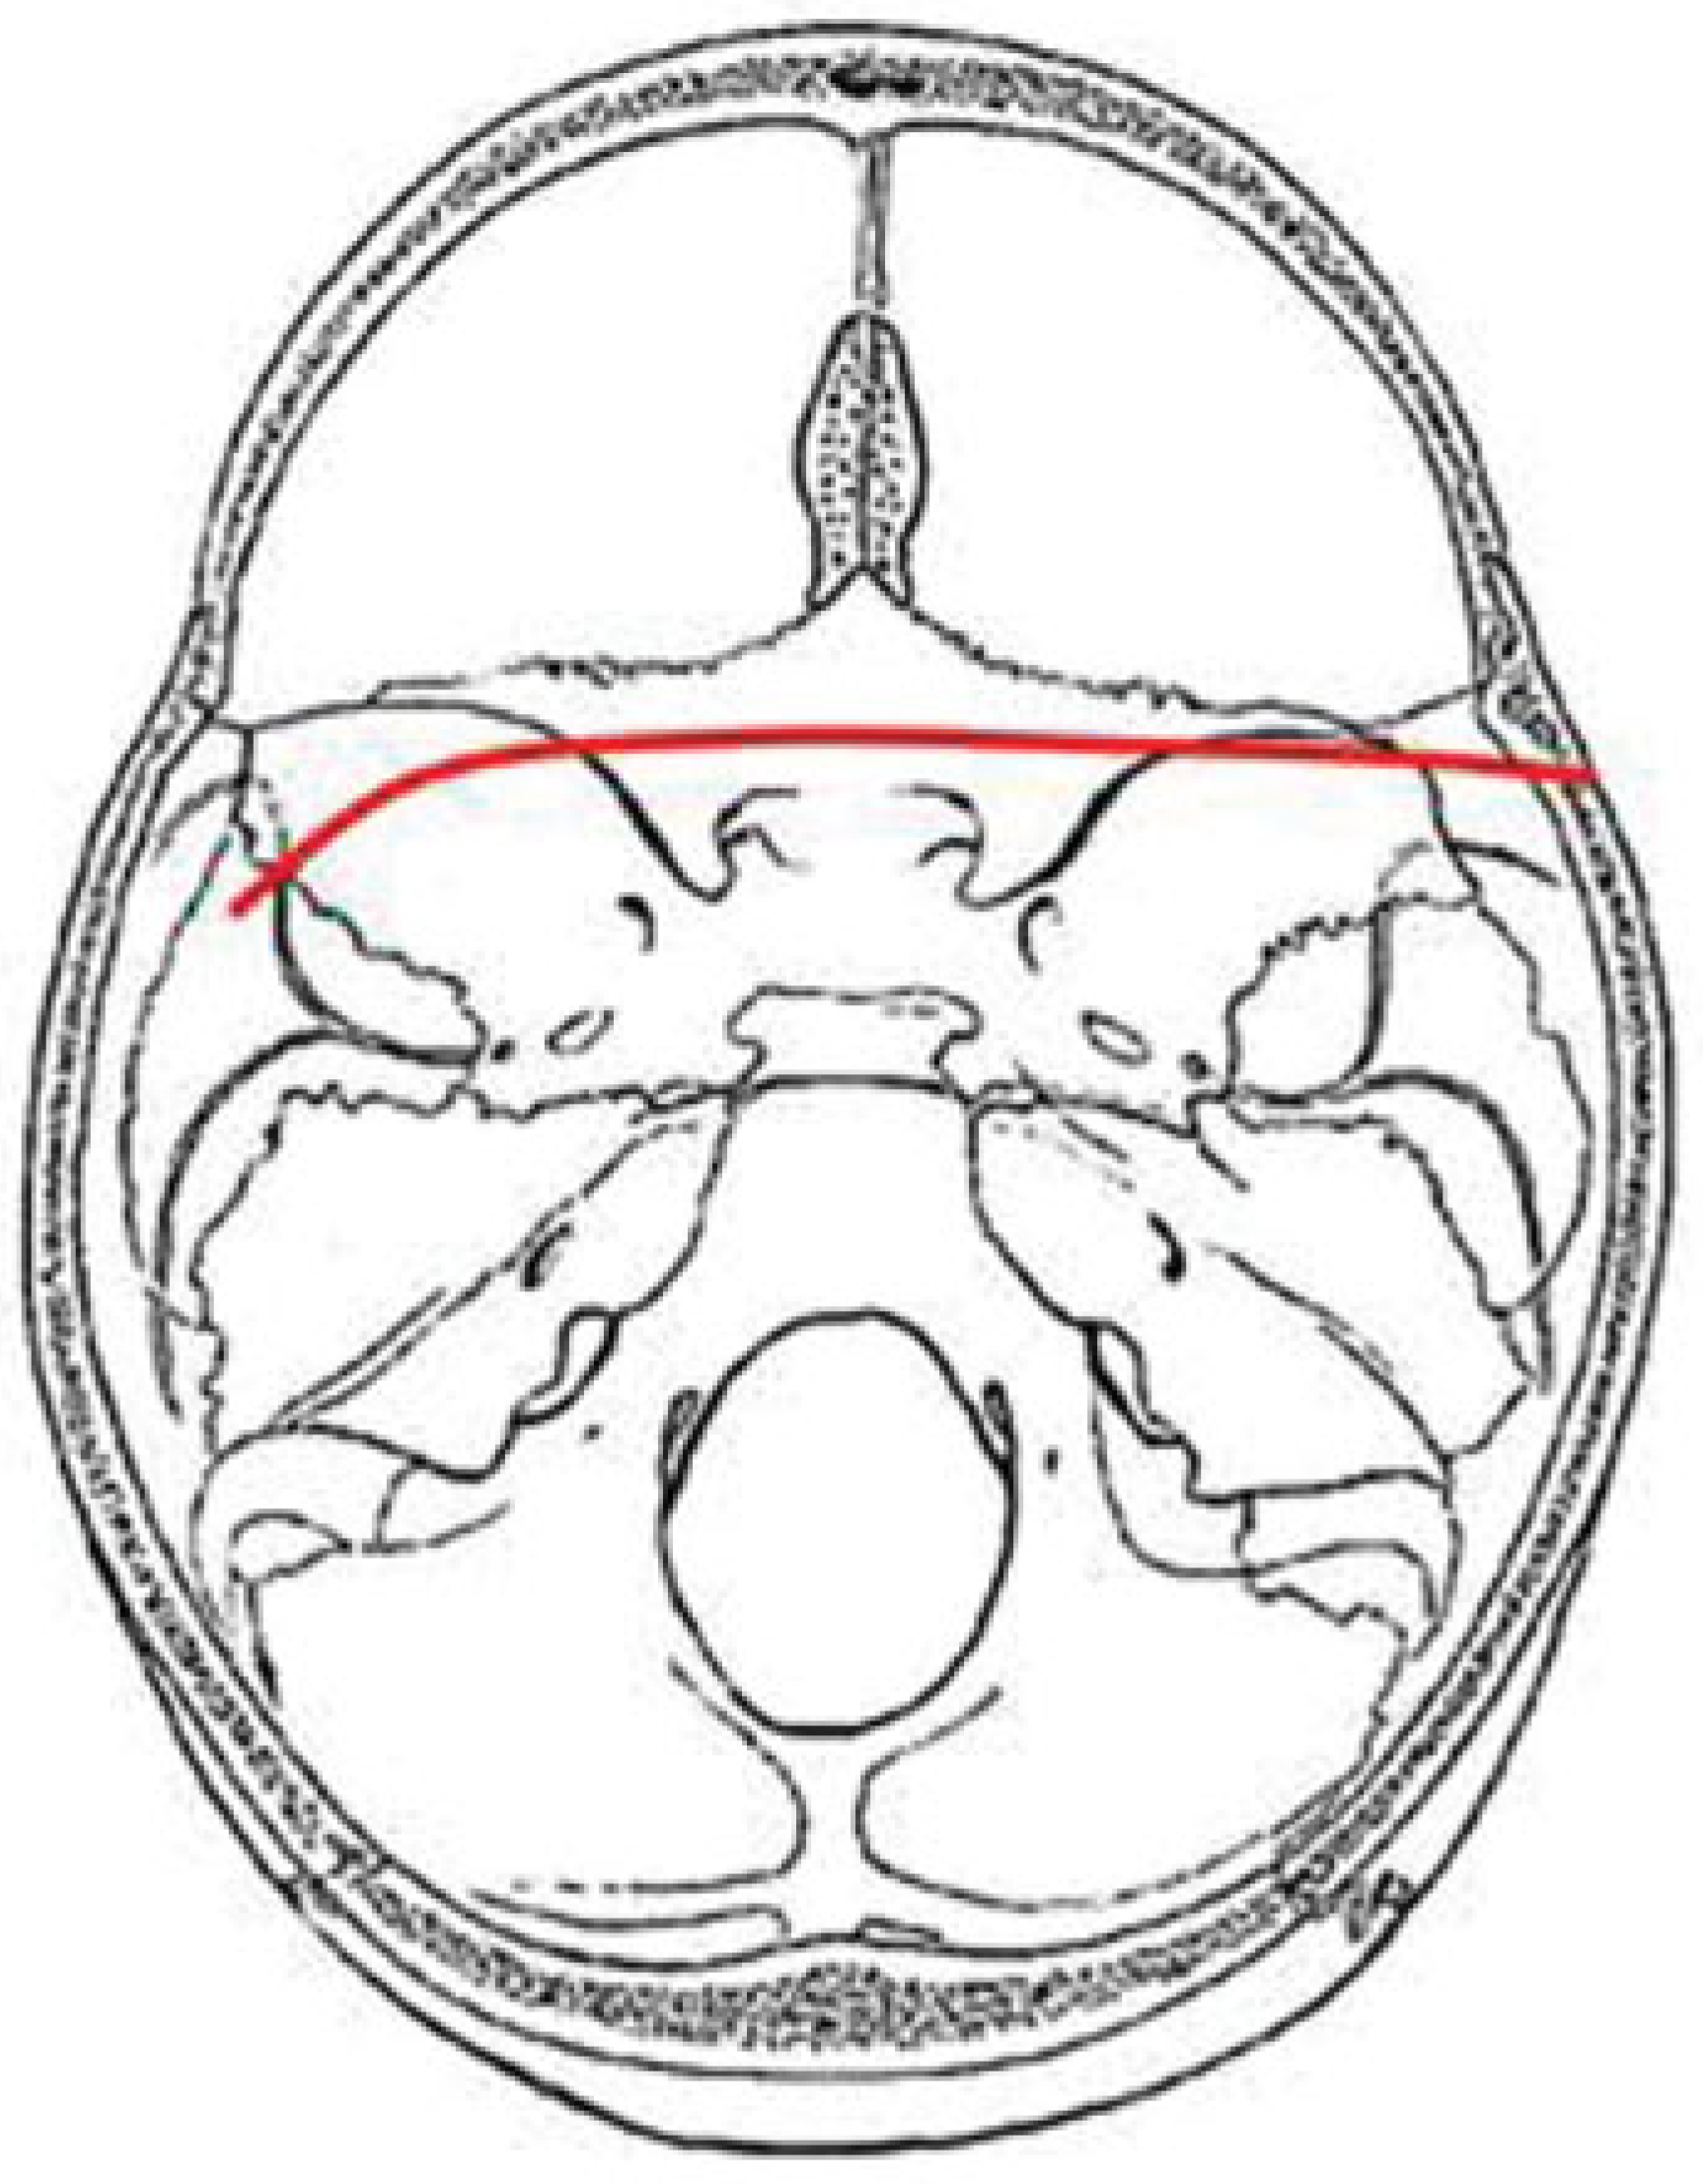

LFD Pattern

The LFD fracture pattern occurs as the result of impact to the lateral frontal region or the anterior malar eminence. Force appears to be transmitted along the lateral orbital and/or lateral maxillary sinus wall to the sphenotemporal buttress. From the sphenotemporal buttress, the force is transmitted along the ipsilateral sphenoid sinus wall to the posterior wall of the sphenoid sinus. The fracture may cross the sphenoid body in a transverse plane or in a diagonally plane. The fracture continues through or immediately anterior to the contralateral carotid canal into the sphenopetrosal syn-chondrosis. The fracture may then continue through the tympanic portion of the temporal bone (Figure 6).

Figure 6. Composite drawing of the lateral frontal diagonal pattern (left impact).